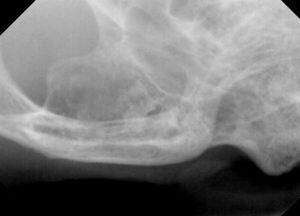

レントゲン検査では、

右上顎臼歯の残根2本と下顎臼歯の残根1本、犬歯は歯冠切除を実施していましたが歯肉に近い場所でした。

レントゲンで確認できる残根を抜歯し、下顎犬歯はより深い場所で切除を実施しました。